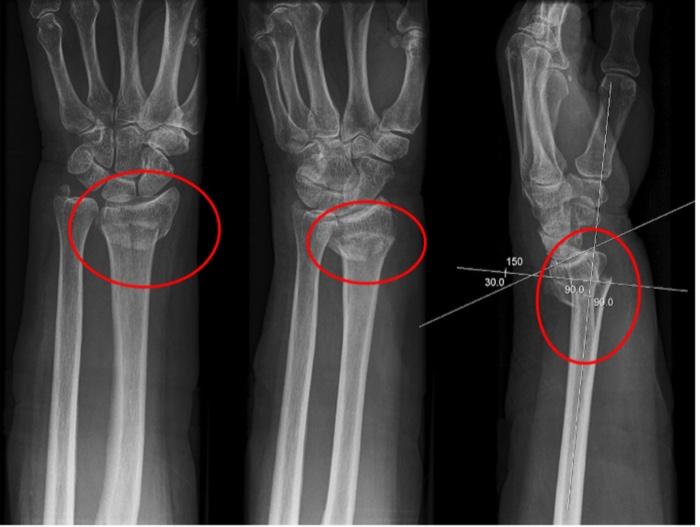

Dinner Fork Deformity MEDizzy